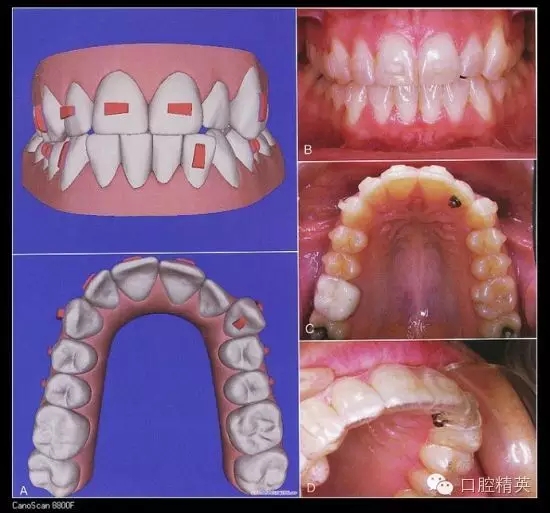

五、隱形矯治器

Invisalign隱形矯治器的原理是先在計算機(jī)里對醫(yī)生的印模進(jìn)行三維建模,按照正畸醫(yī)生的指導(dǎo)來設(shè)計挪動牙齒,得到醫(yī)生的確認(rèn)后投入加工。每付矯治器少量移動牙齒,兩周更換一副矯治器,在1-2年后完成牙齒的矯治。因?yàn)椴馁|(zhì)沒有金屬,受到很多白領(lǐng)的追捧,不過目前還不能夠治療所有的復(fù)雜病例。對付輕中度擁擠,輕度開合,牙縫散開等是不錯的選擇。